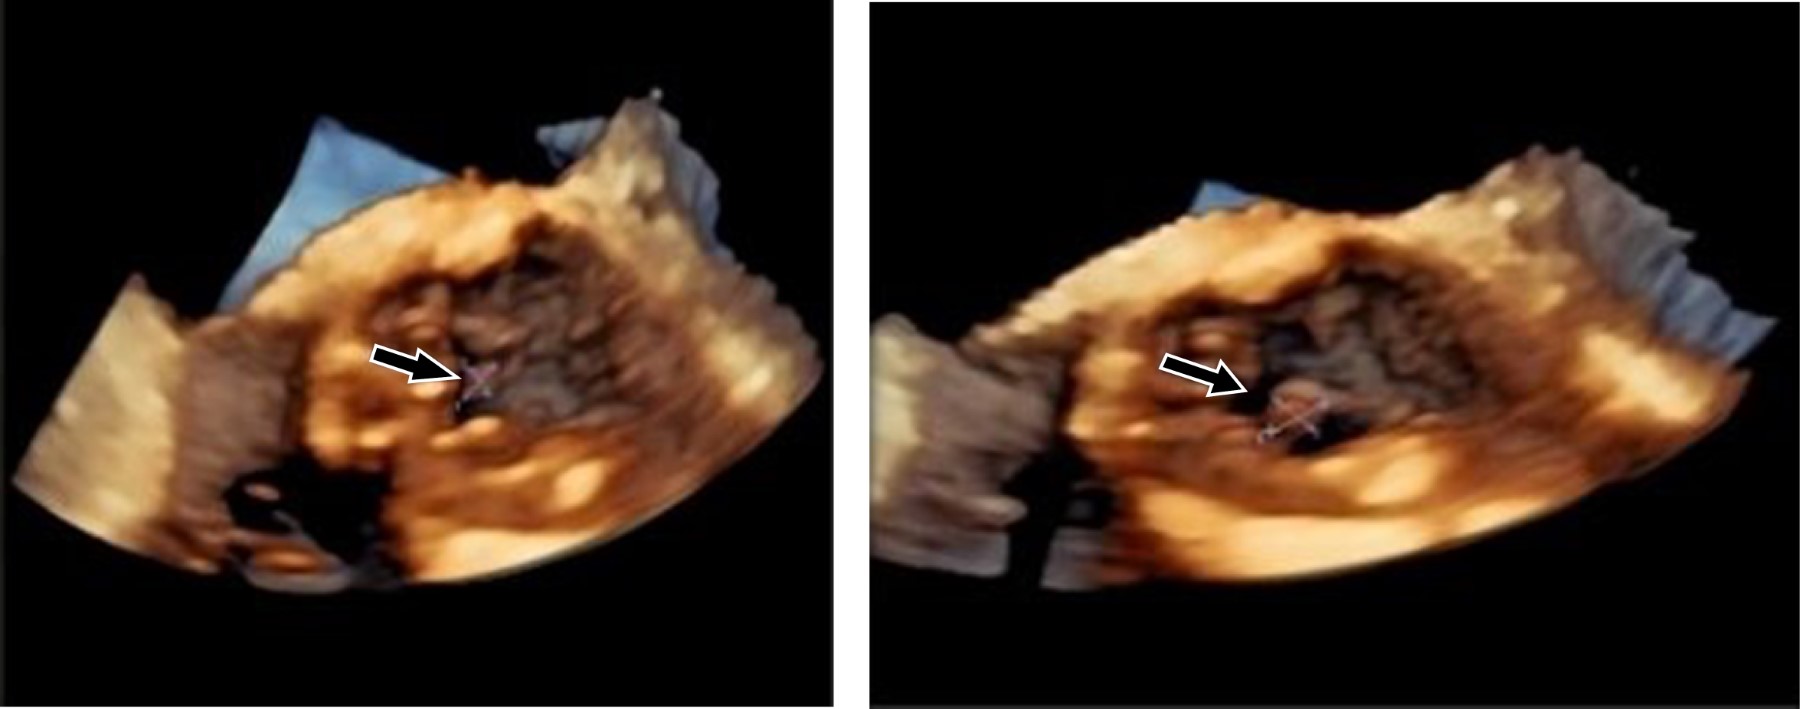

La endocarditis infecciosa en válvulas nativas o en válvulas reemplazadas quirúrgicamente ha sido ampliamente descrita en la literatura; sin embargo, respecto a la endocarditis infecciosa en válvulas bioprotésicas transcatéter, aún se encuentra en un proceso continuo de investigación. Presentamos el caso de una paciente de 66 años con diagnóstico de endocarditis infecciosa temprana de válvula protésica aórtica percutánea SAPIEN 3, quien tuvo una evolución clínica y desenlace favorable con tratamiento médico conservador basado en antibióticos, a pesar de que la incidencia de mortalidad intrahospitalaria a causa de EI-TAVR, representa más de 40%. Reportar nuevos casos clínicos con sus diferentes características, sus tratamientos y resultados obtenidos, se considera de suma importancia para apoyar a un mejor diagnóstico y tratamiento médico en futuros pacientes.

Figura 2